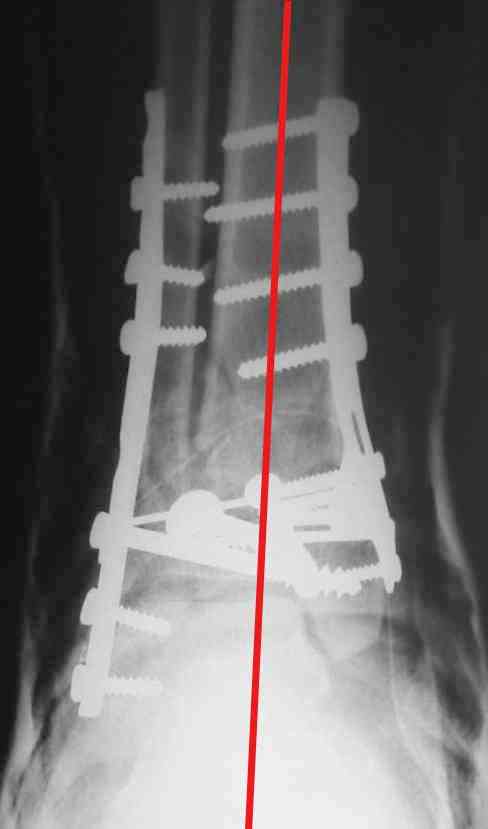

На представленном снимке видно, что эпифиз смещен латерально.

Сейчас с этим ничего не сделать, похоже.

Однозначно сказать сложно.Расстояние между тараном и медиальной лодыжкой меньше чем между тараном и крышей большеберцовой кости.Это может быть за счёт не правильной укладки.Пока не отчаиваетесь.Главное вы поняли принцип.Сделайте несколько проекций прямых и посмотрим.Для всех интересно.С уважением

Мне кажется, что все конечно далеко от идеала. Сложный перелом. Есть ощущение, что малоберцовая кость (ключ!) фиксирована с ротацией и удлинением. Снимки конечно необходимо сделать в правильных проекциях и без гипса...

В голеностопном суставе обязательны 3 стандартные ренгенологические проекции: прямая, латеральная и мортиз. Без них невозможно трактовать состояние голеностопа.

Применение шурурпов 4.5 мм и более толстых пластин крайне недопустимы. Рекомендуется низкопрофильные, контурированные пластины с шурупами 3.5 мм, а иногда те же 3.5 шурупы но с головкой 2.7 мм.